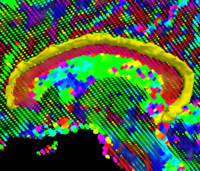

Soft Plaque Detection in CTA ImageryThe ability to detect and measure non-calcified plaques (also known as soft plaques) may improve physicians’ ability to predict cardiac events. This work automatically detects soft plaques in CTA imagery using active contours driven by spatially localized probabilistic models. Plaques are identified by simultaneously segmenting the vessel from the inside-out and the outside-in using carefully chosen localized energies More... New: Soft Plaque Detection and Automatic Vessel Segmentation. PMMIA Workshop in MICCAI, Sep. 2009. | |